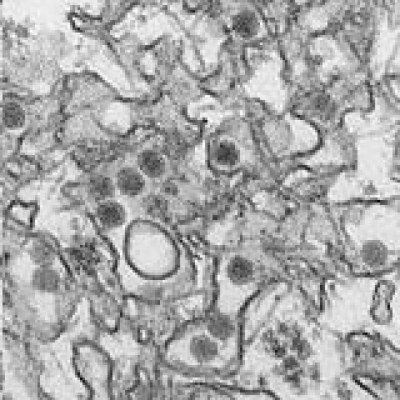

Mientras que las autoridades hondureñas de Salud descartan la alerta, países de Latinoamérica muestran pánico por el zika y su nexo con microcefalia en bebés.

Y es que según la Organización Panamericana de la Salud (OPS) relaciona el nacimiento de bebés con malformaciones congénitas, como la microcefalia (cabeza pequeña), a madres en cuyo primer trimestre de embarazo contrajeron zika.

En ese país también relacionaron el virus del zika con el surgimiento de múltiples casos de microcefalia, una rara malformación que hace que el cerebro no se desarrolle adecuadamente. Además, los científicos también estudian un posible vínculo del zika con el síndrome de Guillain-Barré, que causa una parálisis que puede ser irreversible.